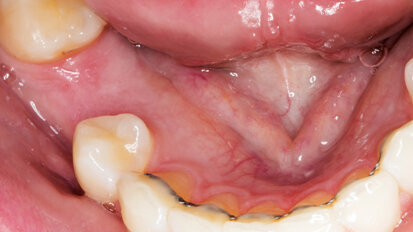

Rehabilitace Straumann